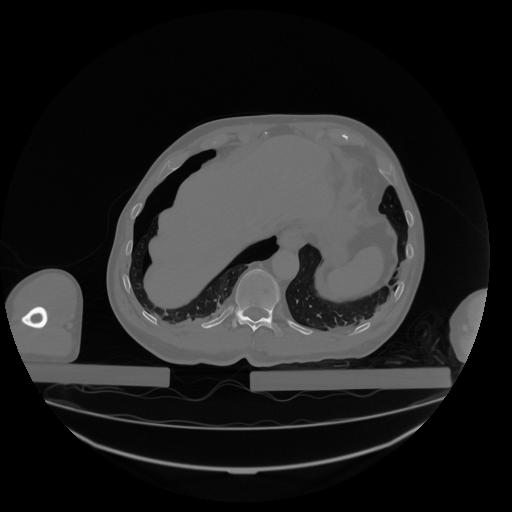

34 CUERPO,CE,Vol,1.0,CUERPO,,